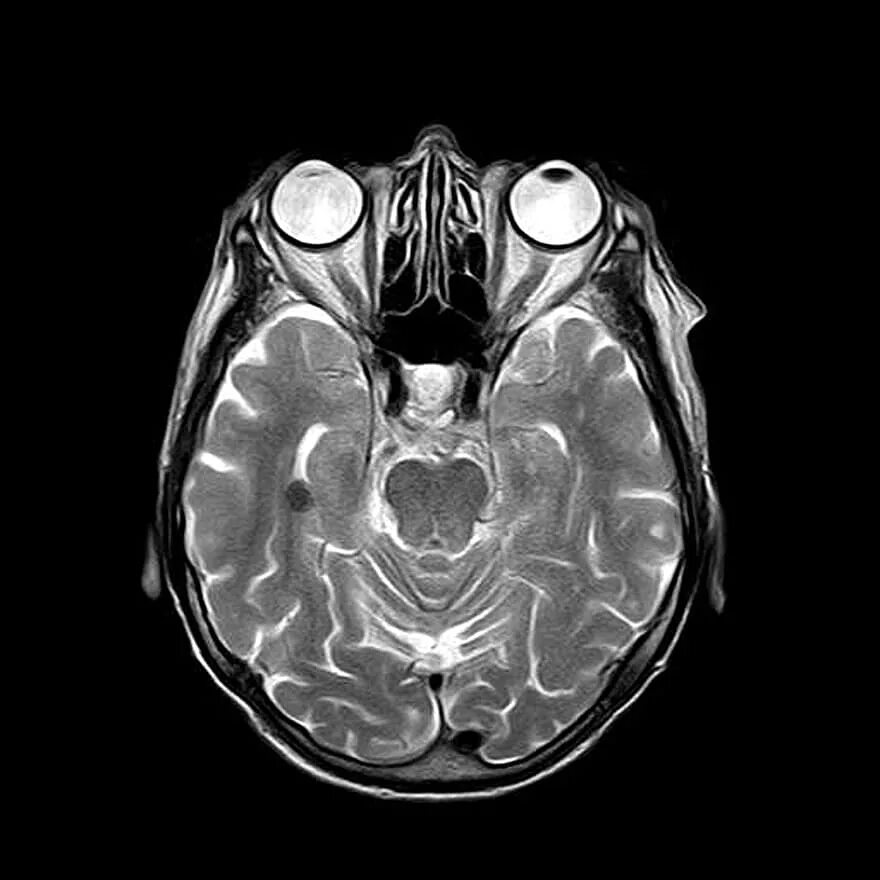

Томограмма головы